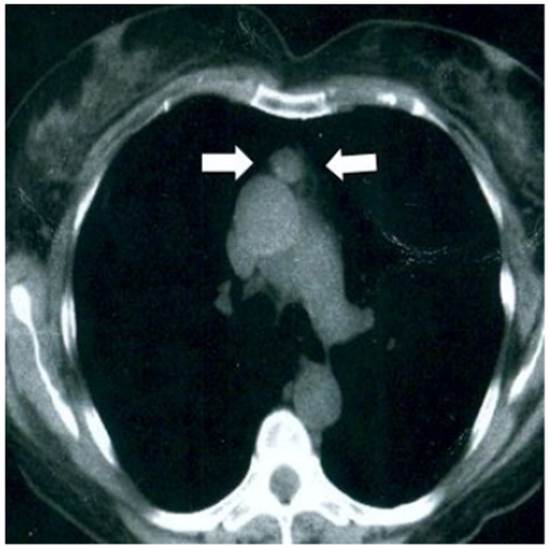

La prueba de densitometría ósea reveló osteopenia en columna lumbar y cuello fe moral (puntaje de T de 1,4 y 1,8, respectivamente), por lo que se realizó el diagnóstico de hiperparatiroidismo primario y se llevó a cabo una investigación adicional para localizar el adenoma. Una gammagrafía con tecnecio-99m sestamibi demostró área de acumulación que indicaba tejido paratiroideo ectópico en el mediastino anterior a nivel del arco aórtico (Figura 1). La tomografía computarizada no mostró anomalías en cuello, pero en mediastino anterior se observó tumoración de 6 x 3 centímetros ubicada en el polo superior de timo (Figura 2), por lo que fue entonces programada para abordaje quirúrgico.

Figura 2 Imagen de tomografía computada de tórax. Las flechas señalan la tumoración en mediastino anterior